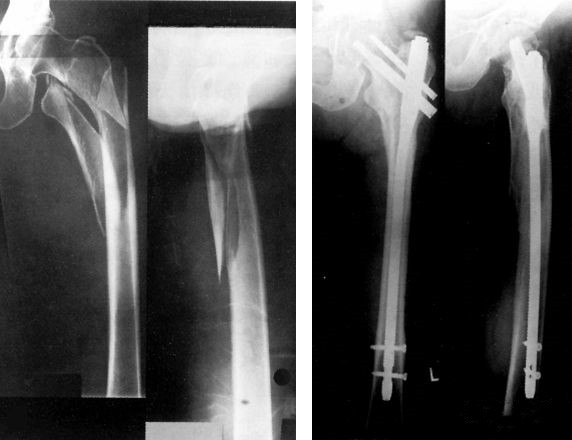

Как только общее состояние пациента находится под контролем, следует выполнить внутреннюю фиксацию, DHS, DCS и PFN.

Перелом шейки бедренной кости, особенно интракапсулярный, может привести к нарушению кровоснабжения головки бедренной кости, поэтому необходимо как можно скорее провести открытую репозицию и внутреннюю фиксацию.

Внутренняя фиксация: < 65 лет

Замена сустава: > 65 лет

Если экстренная операция невозможна, можно выполнить пункцию сустава и аспирацию внутрисуставной гематомы, тазобедренный сустав оставить в полусогнутом и наружном вращении.

Пациентам с тяжелыми повреждениями мягких тканей, открытыми переломами или трудностями в начале операции - надсуставной аппарат внешней фиксации.

Неотложная хирургическая обработка изолированного повреждения — ДКС, ретроградный интрамедуллярный стержень.

Общее состояние больного стабильное, если позволяют местные кожные покровы, операцию следует проводить немедленно.